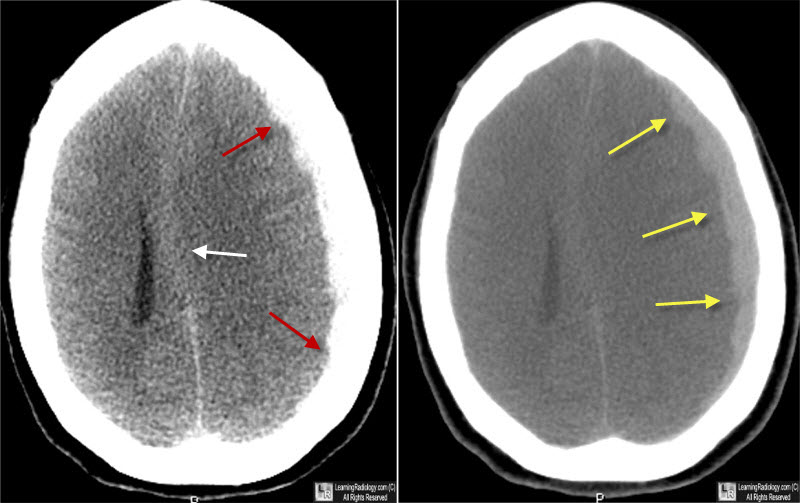

Craniectomía descompresiva versus craneotomía para el hematoma subdural agudo traumático

Encontramos una variación sustancial entre centros en el empleo de la craniectomía descompresiva (CD) versus craneotomía para el hematoma subdural agudo traumático. Esta variación en la estrategia de tratamiento no resultó en un resultado funcional diferente. Estos hallazgos sugieren que la CD primaria debe restringirse a pacientes recuperables en los que no es posible el reemplazo inmediato del colgajo óseo debido a la inflamación cerebral intraoperatoria. eClinicalMedicine, 9 de agosto de 2023.